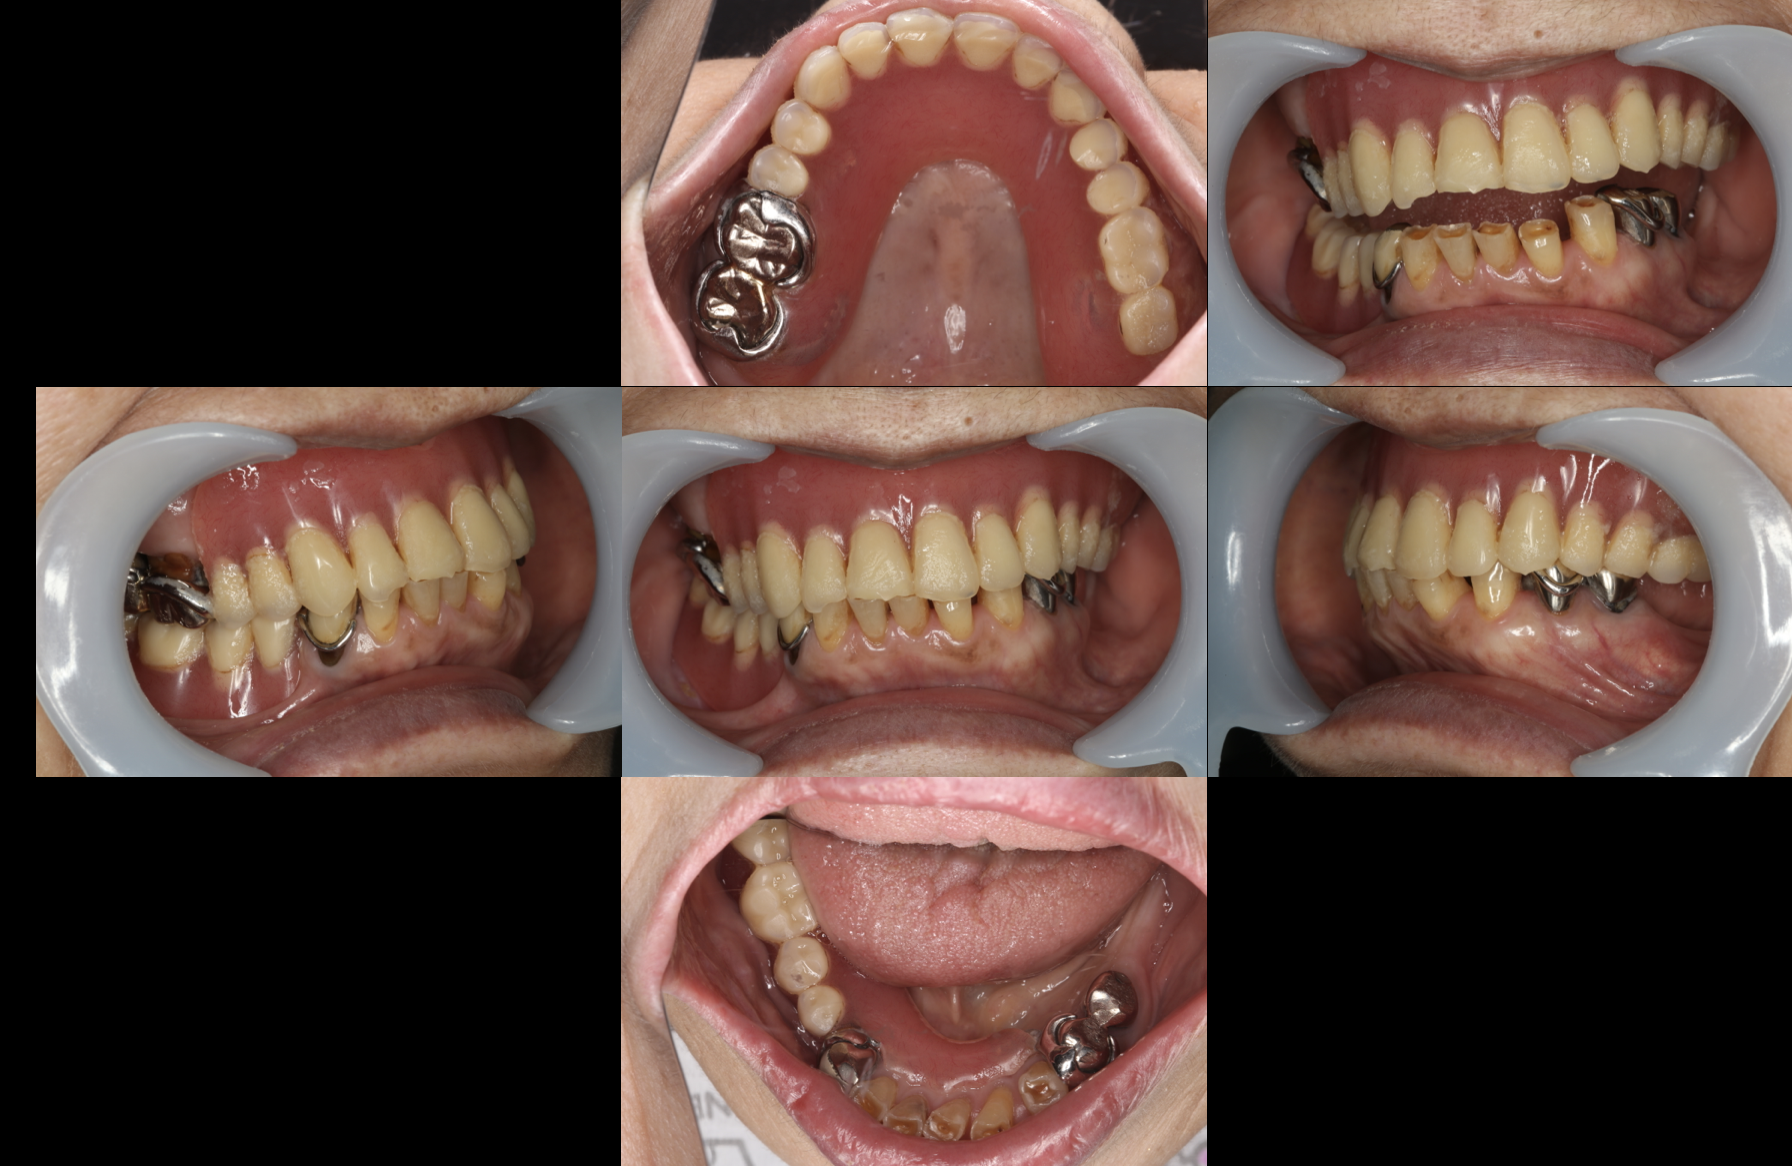

お口の中の写真を撮ったり、

お顔の写真を撮ったり(患者さんの許可を得て掲載しています)、